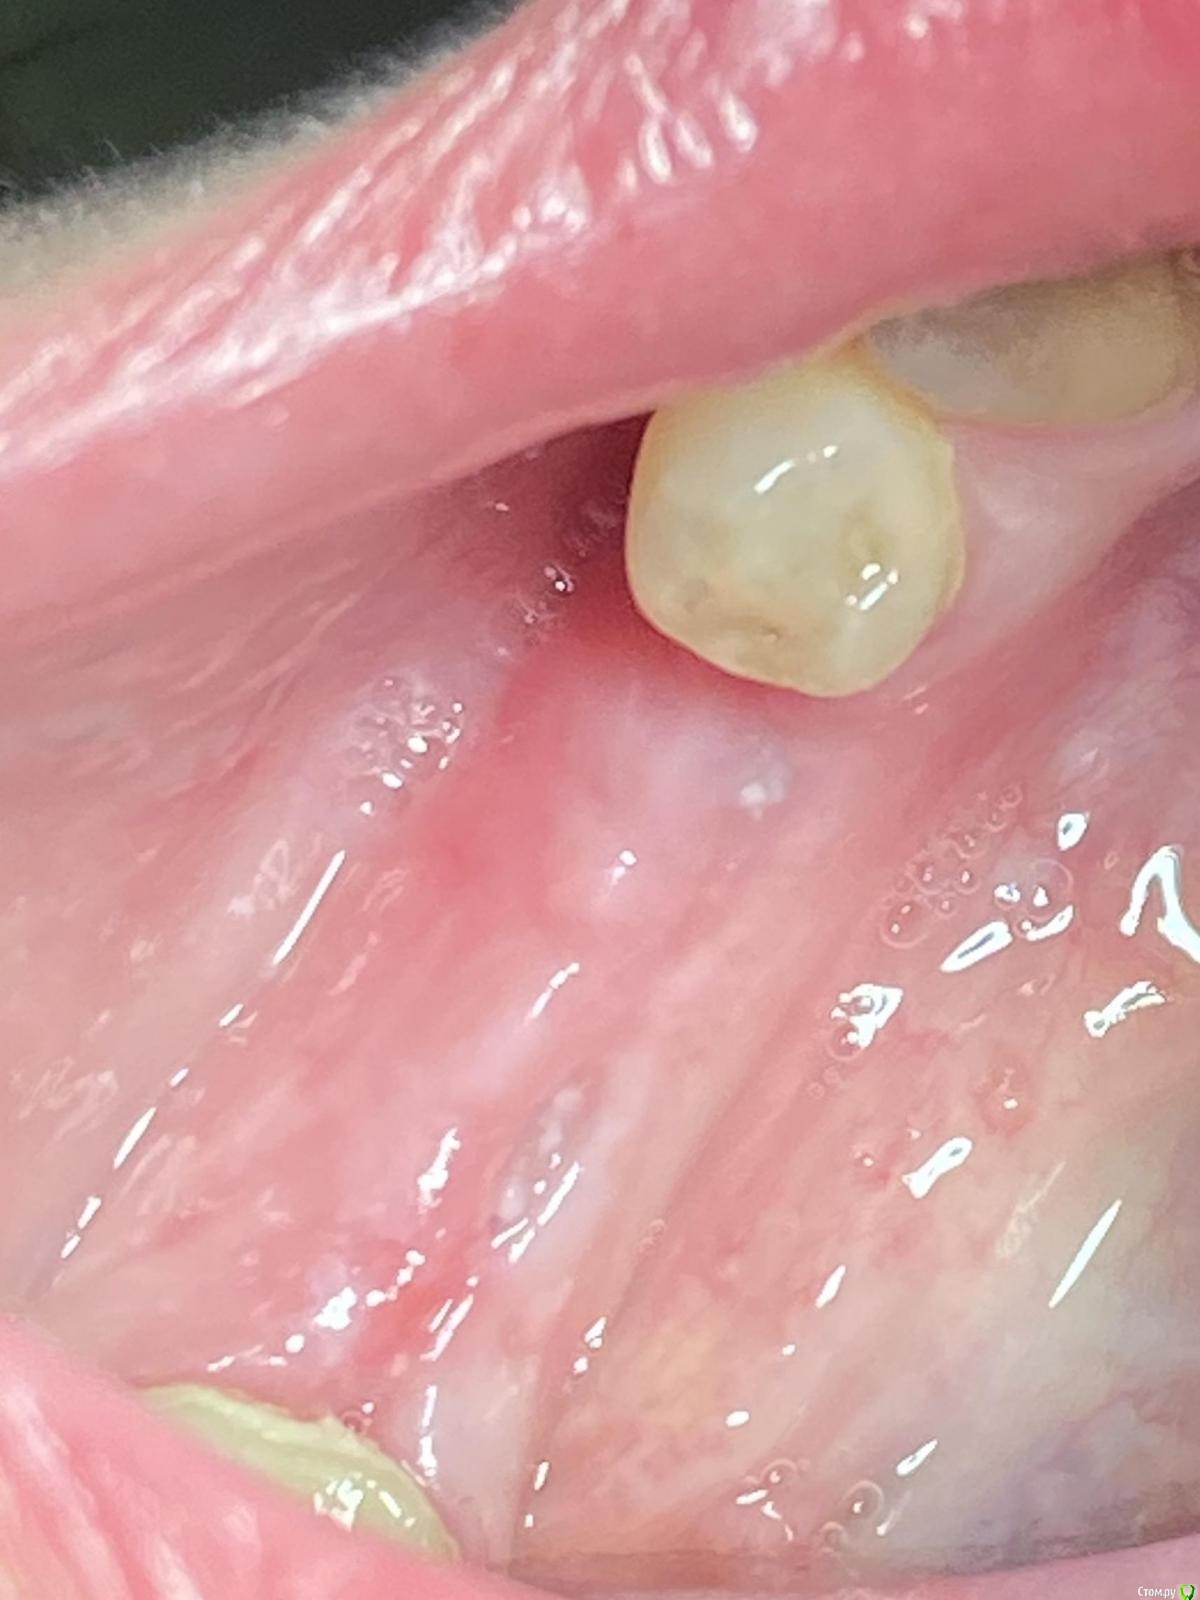

Женька Опубликовано 28 ноября, 2020 Поделиться Опубликовано 28 ноября, 2020 (изменено) Приветствую коллеги. В общем три недели назад 07.11.20 установил пациентке 2 имплантата в позиции 45-46. Гребень по ширине был около 6.5мм в области 4.5 и около 7.2мм в области 4.6 (с учётом заглубления на 1.5-2мм). Это была наверное первая имплантация во время которой я чувствовал себя спокойно и расслабленно. Всё прошло хорошо, немного покопался с непосредственным введением имплантатов, тк никак не хотели топиться на нужные 1.5мм. Поэтому пробовал методику с выкручиванием на пару витков и снова закручиванием. Особого толку не получил, потому взял финальную фрезу и чуть углублял ложе. Так несколько раз, тк боялся всё-таки немного что задену менталис и нлн. Ввиду того, что биотип у пациентки тончайший и язычно было совсем-совсем тонко - заглушки и швы. Назначил нпвс, ванны хг, аб терапию. Но на утро следующего дня пациентка сказала, что чувствует себя шикарно, решили что нпвс оставим, а аб терапию применять не будем (и грешу что в этом мою ошибка).Через неделю сняли швы, всё отлично.Спустя два дня после снятия начались какие-то "костные" боли, как говорит пациентка в области 4.5 импланта. Которые то отпускают, то снова наплывают. На 4.4 есть дефект твердых тканей (на фото виден), но судя по всему беспокоит не он .Пальпация вестибулярно в проекции 4.5 импланта болезненна, небольшая гиперемия, отёка нет. Гигиену пациентка запустила, тк боялась туда залезать и чистить. Снимки прилагаю первые два от 07.11, два последующих 28.11. Ну и внутри ротовые день операции и сегодняшние числа.Похоже 4.5 на выход? своими "туда-сюда" наверняка я нагрел всё что можно... снова расстройство в той работе, где накосячить предельно сложно... Добавка: пить аб ведь сейчас уже бесполезно? Изменено 28 ноября, 2020 пользователем Женька Ссылка на комментарий

Irouil Опубликовано 28 ноября, 2020 Поделиться Опубликовано 28 ноября, 2020 Почему такая атрофия по линии разреза? Ссылка на комментарий

Женька Опубликовано 28 ноября, 2020 Автор Поделиться Опубликовано 28 ноября, 2020 Почему такая атрофия по линии разреза?Может из-за непрерывного шва? Который Ревердена-Мультановского. Ссылка на комментарий